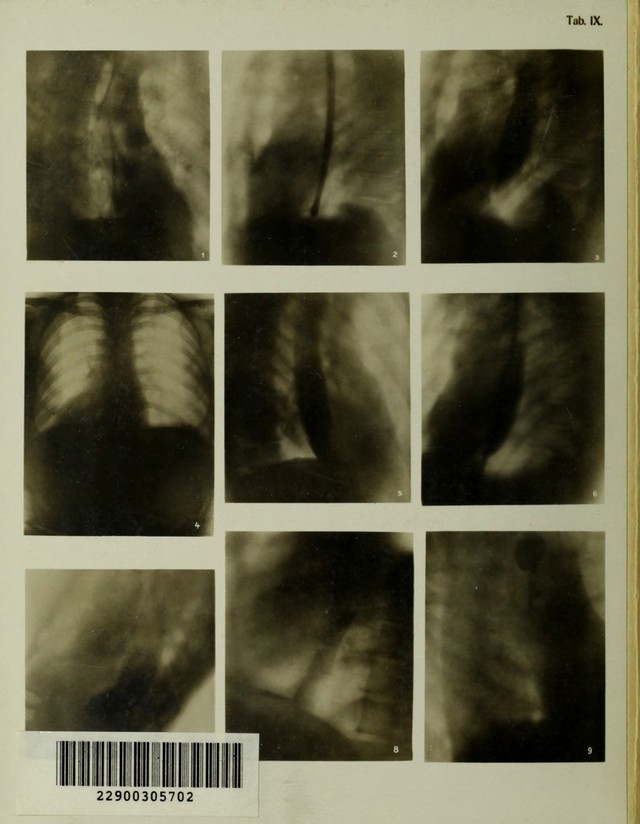

Atlas typischer Röntgenbilder vom normalen Menschen : ausgewählt und erklärt nach chirurgisch-praktischen Gesichtspunkten, mit Berücksichtigung der Varietäten und Fehlerquellen, sowie der Aufnahmetechnik / von Rudolf Grashey.

Credit: Atlas typischer Röntgenbilder vom normalen Menschen : ausgewählt und erklärt nach chirurgisch-praktischen Gesichtspunkten, mit Berücksichtigung der Varietäten und Fehlerquellen, sowie der Aufnahmetechnik / von Rudolf Grashey. Source: Wellcome Collection.